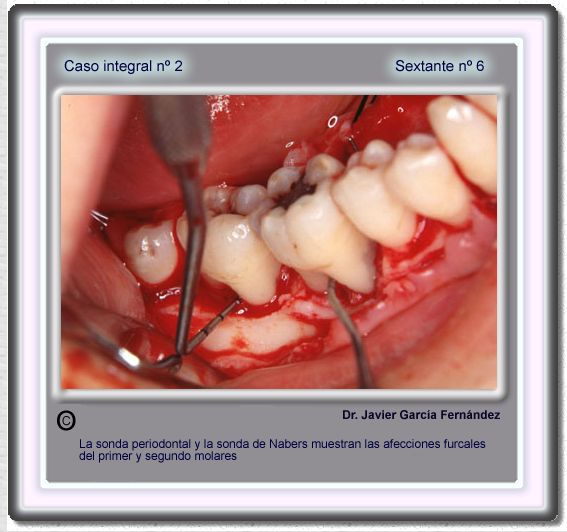

image 78